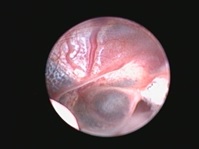

Риноскопия - это эндоскопическое исследование носовых ходов и носоглотки с помощью эндоскопа. Для исследования носовых ходов чаще всего используются жесткие эндоскопы, которые вводятся через ноздри в носовые ходы. Для осмотра носоглотки удобнее применять гибкие эндоскопы, осмотр проводится через ротовую полость. Сама процедура риноскопии проводится с активной санацией физиологическим раствором, что так же оказывает лечебный эффект, особенно при хронических и гнойных ринитах. Во время исследования осматриваются все носовые ходы ( вентральный, средний, дорсальный), а так же полость носоглотки, оценивается цвет слизистой, характер ее повреждений, оценивается проходимость и наличие инородных предметов, кист и новообразований. При обнаружении подозрительных участков слизистой, при хронических ринитах, новообразованиях- проводится взятие материла для гистологического исследования. Гистологическое исследование позволяет поставить более точный диагноз и исключить онкологическую природу заболевания.

Во время риноскопии помимо осмотра проводится и удаление полипов, кист и новообразований. Удаление образований выполняется с помощью специальных эндоскопических инструментов, очень важно, что удаление проводится под эндоскопическим контролем.

Кисты носовых ходов

крупный полип носоглотки

удаленный полип